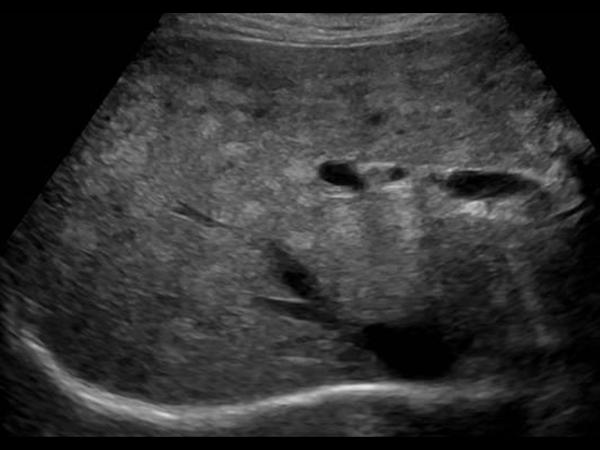

Gan nhiễm mỡ

» Thông tin: Nữ giới – 59 tuổi.

» Lâm sàng: Kiểm tra sức khỏe.